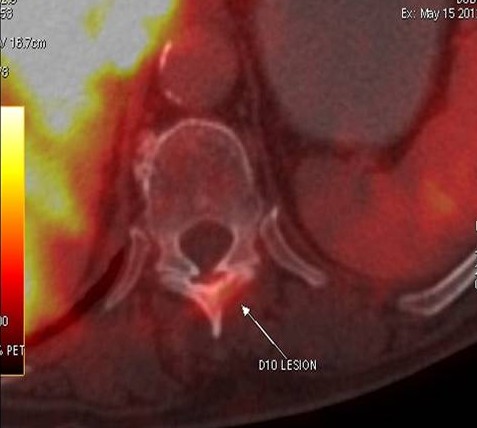

CT scan of the abdomen confirmed the findings ; For further clarification PET whole body scan was done at a centre in Chennai. The following images are from that.

Focal FDG avid lesion in left lamina of D10 – possibly metastatic.